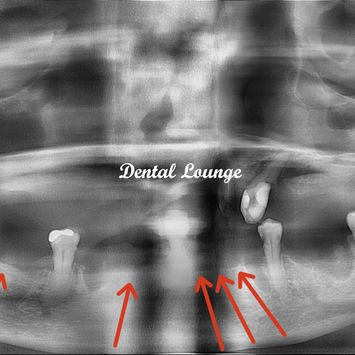

Retained roots: #32, #35, #36, #44.

Local anesthesia (LA) removal of retained roots #32, #35, #36, #44.

Pre-operative CBCT taken.

Post-operative CBCT taken.

No tooth remnants noted.